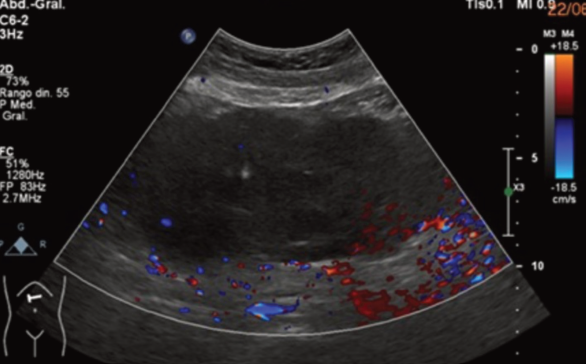

Se encontró leucocitosis, por lo que se pensó en colecistitis aguda, solicitando ultrasonido, en el que se observó lesión heterogénea de predominio hipoecoico, con zonas anecoicas difusas en su interior, ovoidea, de bordes lobulados, localizada en epigastrio con extensión hacia flanco derecho, con dimensiones en sus ejes mayores de 10.8 × 15 × 7 cm. En Doppler color se observó aumento de la vascularidad periférica, de origen por determinar, sin descartar etiología neoplásica (figuras 1a, 1b y 2).

Imagen: Argüello Ramírez et al.

Figura 2 Ultrasonido Doppler color que muestra imagen heterogénea, con aumento de la captación periférica.